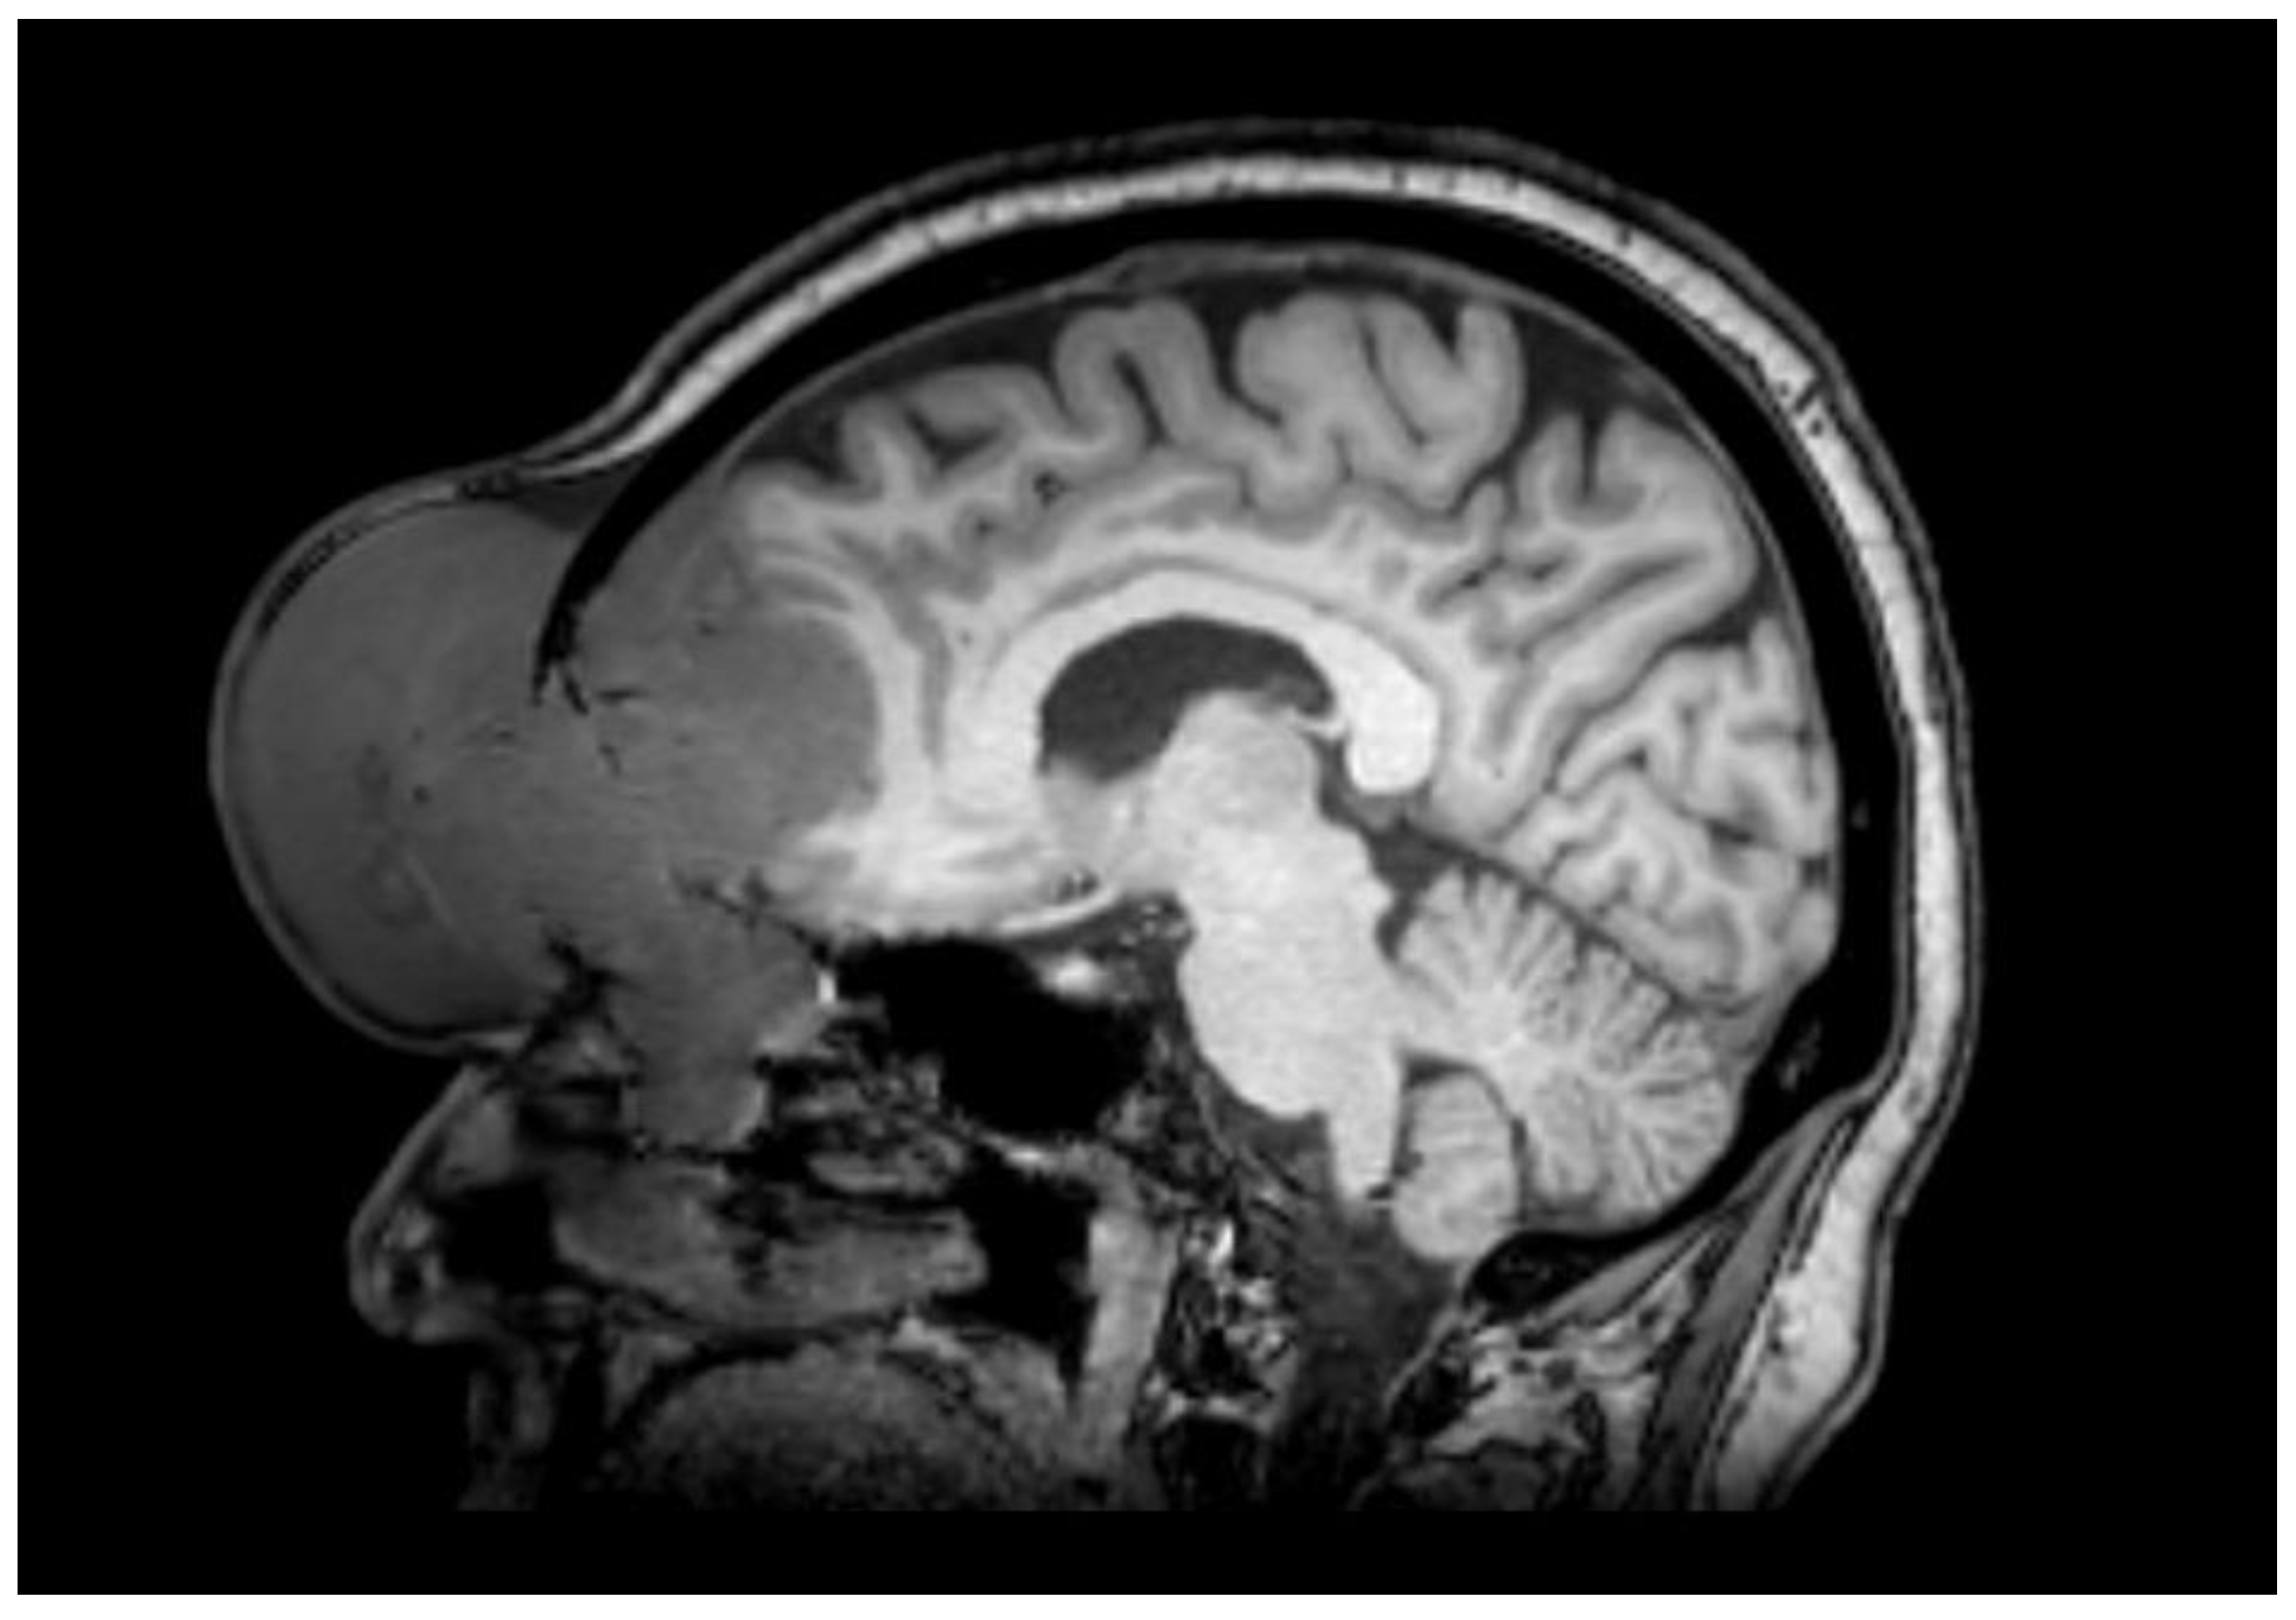

2. Case Report